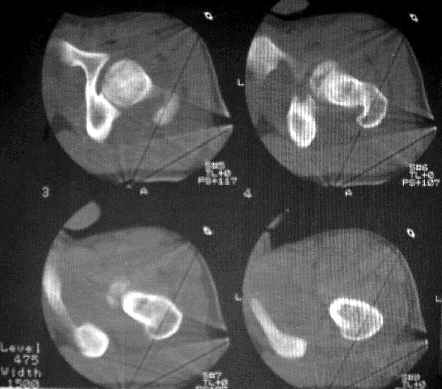

После рентген дообследования складывается мнение об отрыве дистального конца связки головки бедра с костным фрагментом головки (КТ2 скан 3, 4, КТ3 скан 1, прямая проекция - нижнийот 19.05). Данный вариант травмы встречается не часто, но известен, если мне не изменяет память, например см. Мюллер М.Е., Алльговер М., Шнайдер Р., Виллинеггер Х. Руководство по внутреннему остеосинтезу. - Springer-Verlag, 1996. - 750 с. С моей точки зрения, оптимально было бы остеосинтез головки, в обязательном порядке с сохранением целостности связки головки бедра. Как это технически выполнить - вопрос не простой. Кто знает и делал ???

Несколько соображений к "картинкам". На прямом снимке и КТ-томограммах все типичные линии вертлужной впадины: крыша, передняя стенка, задняя стенка - сохранены. На КТ-сканах 6 и 7 появляется фрагментация головки. С учетом R-томограмм отломок расположен спереди-снизу, а не сзади-сверху от сустава, как написано в описании КТ.